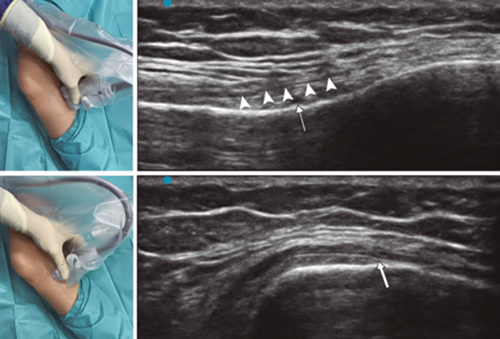

Radiofrecuencia de los nervios geniculados guiados por ecografía

Aún no está claro qué método de imagen es superior como guía para realizar RFTNG, pero hay autores, como Kim y cols. (16), que concluyen que la ecografía podría ser el instrumento de elección. En su estudio no encontraron diferencias en la eficacia del bloqueo de nervios geniculados (BNG) al realizarlo de forma ecoguiada o guiada con fluoroscopia. Estos autores localizaron de forma ecoguiada los nervios geniculados y posteriormente realizaron imágenes con fluoroscopia más contraste, demostrando que las dianas para realizar el BNG se localizaban de forma similar independientemente del método de imagen usado. El alivio del dolor, la mejoría funcional usando la escala WOMAC (Western Ontario and McMaster’s Universities Osteoarthitis Index) y la seguridad fue similar en ambos grupos (16).

Para lograr una correcta ubicación de las referencias anatómicas por ultrasonido debemos colocar al paciente en posición supina con la rodilla flexionada y una almohada debajo de la fosa poplítea (14,16,19). Después de realizar asepsia/antisepsia de la rodilla, colocación de campos quirúrgicos y de la funda estéril del transductor lineal de alta frecuencia, procedemos a ubicar el NGSM (Figura 3). Colocando la sonda en un plano coronal sobre la cara interna de la rodilla, la deslizamos en sentido craneal hasta visualizar la unión de la metáfisis con la diáfisis femoral y la arteria/nervio geniculado superomedial (ANGSM), usualmente están localizados cerca al periostio del fémur (en caso de no encontrar esta estructura neurovascular, se toma como referencia la unión de la metáfisis y la diáfisis femoral). Después se marca en la piel el punto medio del transductor que corresponde a la ANGSM y se gira el transductor para ubicarlo en el plano transversal o axial para visualizar la ANGSM en eje corto (si no es posible la visualización de esta estructura, confirmar que estamos a un 50 % de la profundidad del fémur). En este corte transversal se avanza la aguja de RFT en plano desde anterior a posterior hacia la ANGSM o hasta una profundidad del 50 % del espesor del fémur. Finalmente se vuelve a girar el transductor 90°, dejándolo en un plano coronal para comprobar que la punta de la aguja está cerca de la ANGSM o de la unión de la metáfisis y la diáfisis femoral (14,16,19).

Fig. 3. Sonoanatomía y técnica para realizar el bloqueo del nervio geniculado superomedial (NGSM). El transductor se ubica en el eje largo distal del fémur y una vez que se tenga la posición del NGSM (asteriscos), se gira la sonda 90 grados para obtener una visión en eje corto del fémur (no olvidar mantener la misma profundidad a la que encontramos el NGSM en el eje largo). VM: vasto medial.

Para ubicar al NGIM (Figura 4) colocamos el transductor en un plano coronal sobre la cara interna de la rodilla, lo deslizamos en sentido caudal hasta identificar la unión de diáfisis con la metáfisis tibial y la arteria/nervio geniculado inferomedial (ANGIM), y repetimos los mismos pasos que usamos para el NGSM. En caso de no encontrar la ANGIM, la referencia que se tomará será la profundidad del 50 % del espesor de la tibia (14,16,19).

Fig. 4. Sonoanatomía y técnica para realizar el bloqueo del nervio geniculado inferomedial (NGIM). El transductor se ubica en el eje largo proximal de la tibia e identificamos el paquete vasculonervioso del NGIM (flecha) justo debajo ligamento colateral medial (puntas de flechas). Luego se gira la sonda 90 grados para obtener una visión en eje corto de la tibia (no olvidar mantener la misma profundidad a la que encontramos el NGIM en el eje largo).

Para ubicar el NGSL, el paciente debe estar en posición supina con el miembro inferior en rotación interna, consiguiendo una buena exposición de la cara lateral del muslo. Colocamos el transductor lineal en un plano coronal sobre la cara lateral de la rodilla, lo deslizamos en sentido craneal hasta visualizar la unión de la metáfisis con la diáfisis femoral y la arteria/nervio geniculado superolateral (ANGSL), y repetiremos los mismos pasos que usamos para el NGSM (14,16,19).

Después comprobamos que el umbral de estímulo sensitivo a 50 Hz que desencadene una parestesia o dolor sea menor de 0,6 V, y para evitar daño de nervios motores no debe existir fasciculaciones del miembro inferior con un estímulo motor a 2 Hz con 2,0 V. Si todo está correcto, administramos 2 ml de lidocaína al 2 % o mepivacaína al 2 % en cada nervio y procedemos a realizar la RFT a 80 °C durante 90 segundos (9,14).

En nuestra revisión encontramos otras referencias anatómicas que nos pueden ayudar a localizar los nervios geniculados. Yasar y cols. (20) identificaron que el NGSM se localiza un centímetro anterior al tubérculo aductor, el NGIM se localiza en el punto medio entre el pico del epicóndilo tibial medial y el inicio de la inserción de las fibras del ligamento colateral medial sobre la tibia.